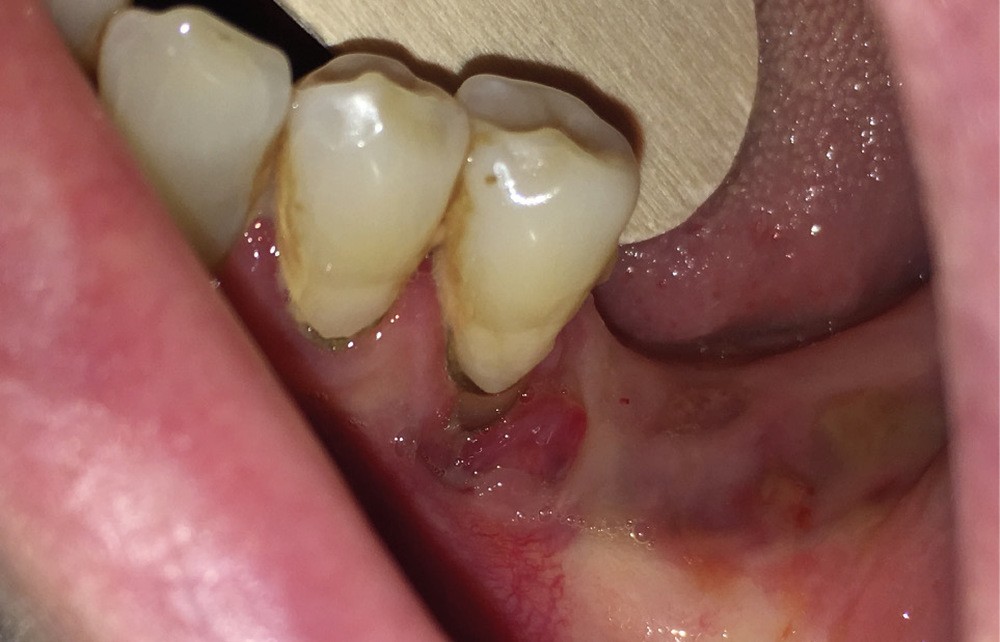

Dans le bilan avant mise en place du traitement, les recommandations, notamment de rhumatologie, indi-quent la réalisation d’un bilan dentaire et la mise en œuvre des soins nécessaires [1]. Cela a pour but d’identifier les foyers infectieux en présence et de les prendre en charge avant que le traitement ne débute, donc avant que le patient présente un risque infectieux accru (fig. 2).

L’attitude face à ces foyers infectieux, au-delà du pronostic de chaque dent, dépendra de facteurs, généraux notamment : thérapeutique mise en place (donc risque infectieux précis pour le patient), durée estimée du traitement (et donc du risque), le pronostic de la pathologie, la présence de facteurs de risque majorant le risque infectieux ou encore la compliance du patient [2].